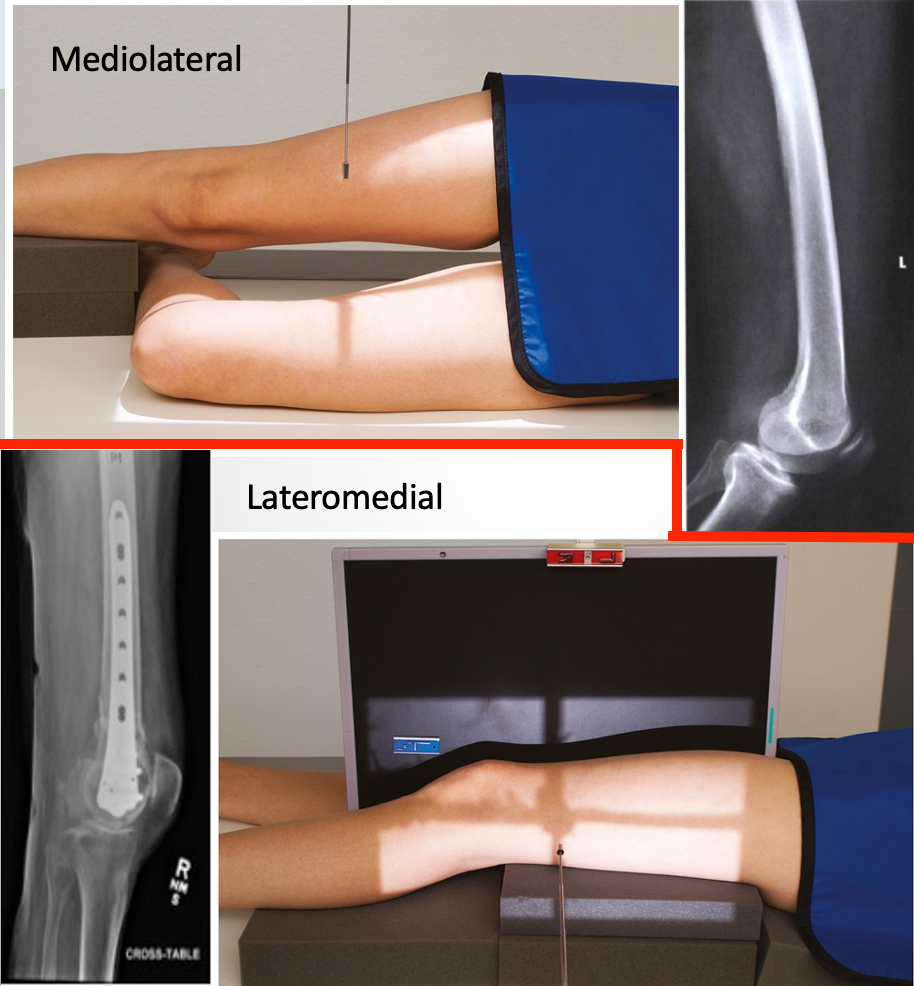

Lateral Tib/Fib

• IR 14x17 portrait or diagonal, 48 SID

• Pt in lateral recumbent position on affected side. Place unaffected leg behind (or across) affected leg. (across works well for knee). Ensure true lateral position by evaluating plane of patella & have it perpendicular with IR. Ensure 1”-2” of knee and ankle joint on IR for divergent rays.

• CR perpendicular to midpoint of tib/fib